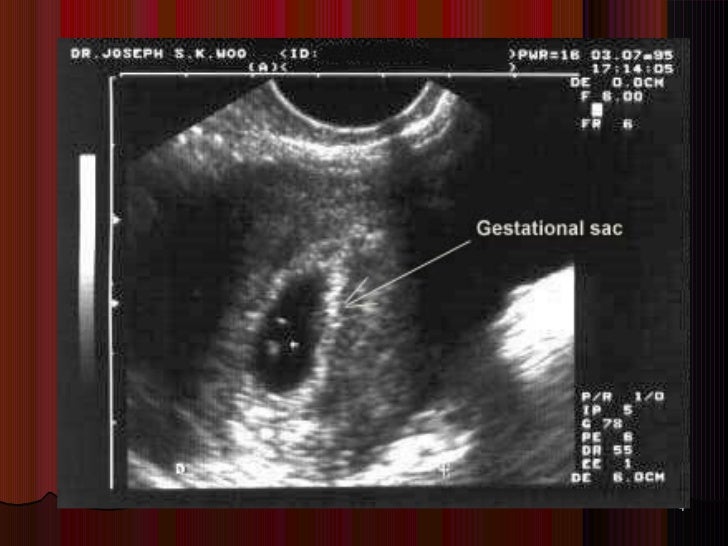

Беременность утолщение одной стенки матки по узи - фото презентация